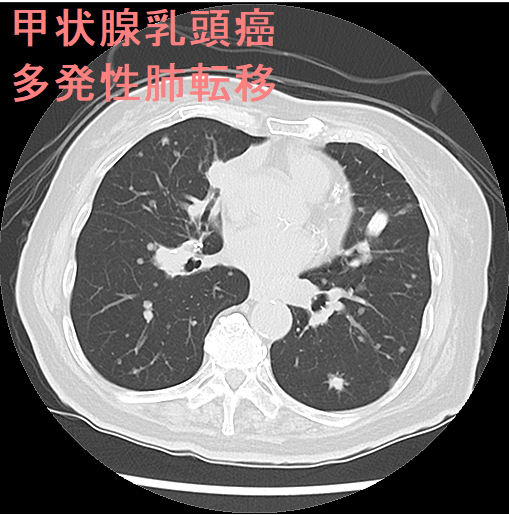

甲状腺乳頭癌 肺転移 CT画像。中-下肺野に、小粒状陰影が多数あります。

甲状腺癌の肺転移様式として、両側肺に、びまん性多発小結節を形成するのが普通です(上記肺X-p、CT画像)。孤立結節型は11.4%とされます。

甲状腺乳頭癌の多発性肺転移に伴い、胸膜転移(胸膜播種、癌性胸膜炎、癌性胸水)が起こります。ただし、肺転移を認めないのに対側(甲状腺癌が無い側)に起こる場合もあります。